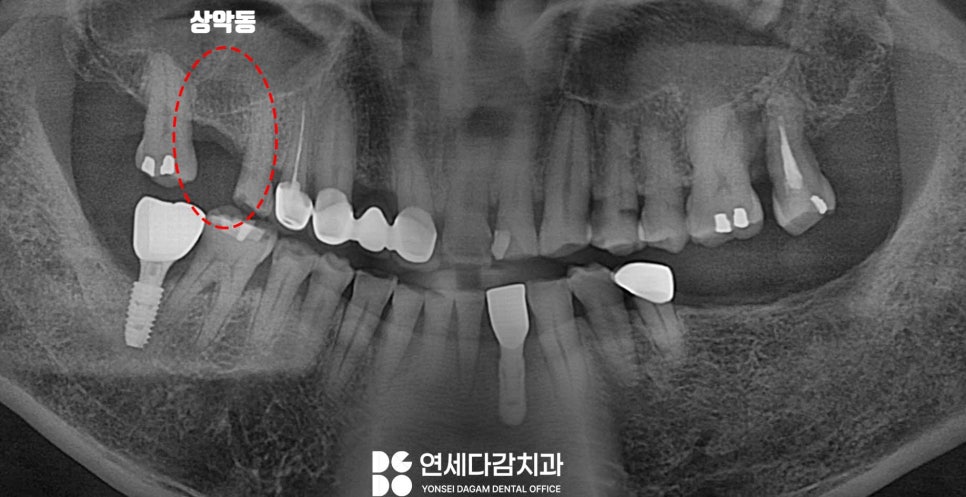

이럴 때 CT를 보면 뼈 높이가 낮아

상악동이 손상될 위험이 높다는 말을 듣게 되죠.

발치 후 생기는 구강 변화

어금니를 뽑은 후 잇몸뼈는

사용하지 않는 뼈라고 받아들여

점차 잇몸뼈가 흡수되는 변화가 일어납니다.

노화가 진행될수록 상악동이 확대되는

함기화라는 현상까지 더해진다면

잇몸뼈 높이가 더 줄어들게 되겠죠.

그 결과 임플란트를 심을 수 있는

잔존골 높이가 2~3mm 정도로

현저히 부족해지는 경우가 있습니다.